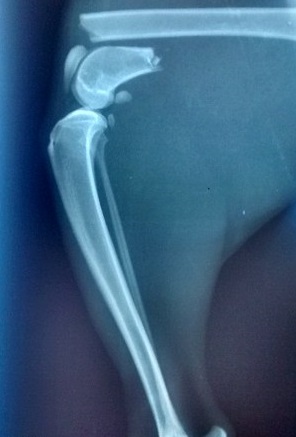

LONDRA – Un gatto è volato giù da un palazzo compiendo un salto di circa 30 metri. Il felino ha riportato una frattura delle gambe posteriori, un polmone collassato e il femore rotto.